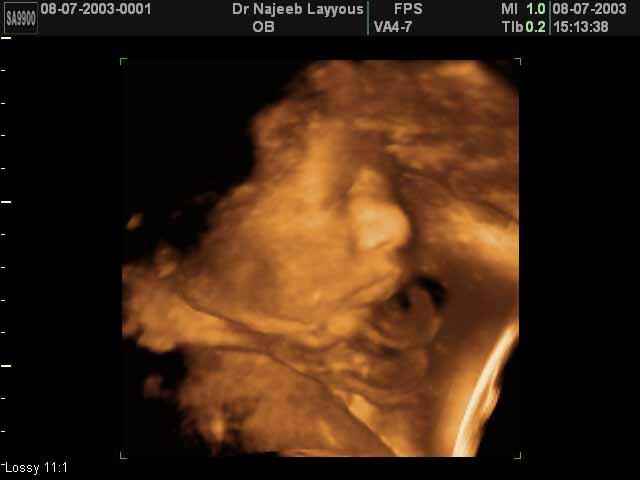

- 3D Fetal Profile Ultrasound Scan Photos

3D Fetal Profile Ultrasound Scan Photos | Dr N Layyous